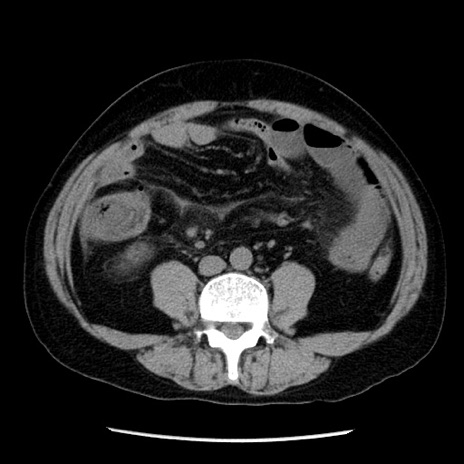

症例29(横断像)

【症例】40歳代男性

【現病歴】2日前から胃痛あり。徐々に周期的な激痛に変化した。本日になっても激痛があるため受診。

【身体所見】意識清明、BT 38-39℃台あり、腹部:膨満、やや硬、右下腹部に圧痛あり。

【データ】WBC 8500、CRP 23.26